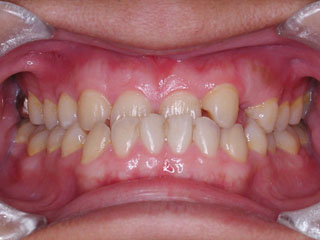

主訴:前歯の歯並び

診断名:開咬傾向を伴う叢生

年齢:31歳

使用した主な装置名:マルチブラケット装置

抜歯/非抜歯および抜歯部位:抜歯(上顎左右第一小臼歯、下顎左右第二小臼歯)

治療期間:動的処置2年6か月、経過観察3年

費用の目安:90~140万円

リスク、副作用:抜歯によるリスク、マルチブラケット治療に伴う歯根吸収など偶発症が発生するリスクがある。

開咬と叢生が見られます。どうやら左右小臼歯間の歯は、それまでの人生でほとんど使われてこなかったようです。なので通常ですと、萌出してきたらほどなく消えてしまう前歯の先端のギザギザ(切縁結節)がそのまま残っています。概ねこのような開咬の場合は、前歯で噛もう噛もうとしているため、臼歯部を回転中心にした顎位のズレを生じている事が多いです。中心位マウントの咬合器やCPI測定で、更に大きな開咬である事が見つかります。

むりやり非抜歯で並べると、まるで前歯が噛まなくなったり、さらに顎をずらして噛む人になってしまいますので、小臼歯抜歯で対応しています。このケースでは下顎の非対称も見られるのですが、治療メカニクスが不十分であったため、正中変位の改善が達成されませんでした。しかし開咬傾向が強いケースでは、できるだけ顎間ゴムは使わない事にしています。なぜなら、そのようなメカニクスは多かれ少なかれ、顎関節のズレを生じさせると考えられるからです。今時分なら、歯科矯正用アンカースクリューのメカニクスを用いて改善しているでしょう。